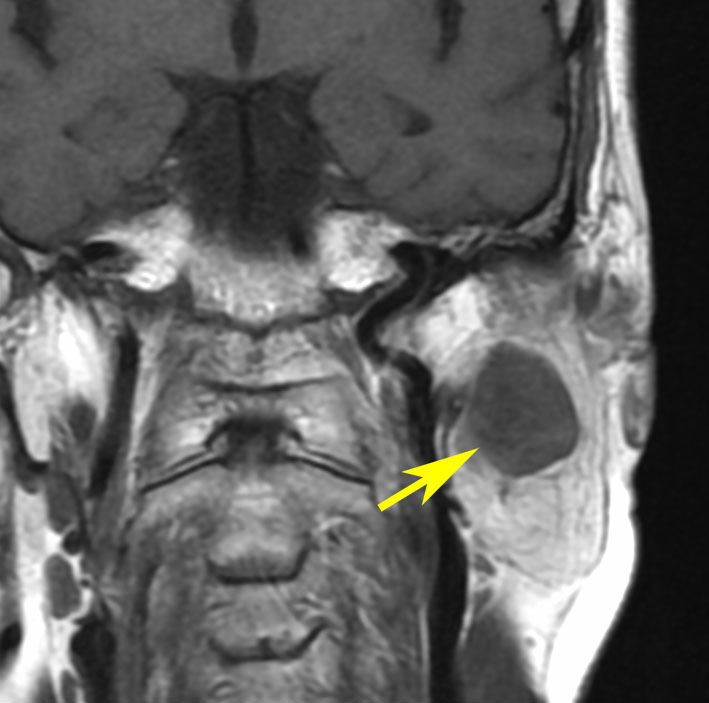

側頭骨内(顔面神経垂直部)

20代の男性で,下顎と口腔内の軽度の感覚以上だけがありました。聴力は正常で顔面神経麻痺は全くありません。でもこれは巨大な顔面神経鞘腫です。手術前は三叉神経鞘腫を疑っていました。

内耳道が少し拡大して内耳道内にも腫瘍があります。

手術摘出しましたが,聴神経は正常に見えて手術後も聴力は保たれました。三叉神経からは完全に剥離できています。

腫瘍の外側表面で顔面神経は紙のように薄くなって(菲薄化して),モニターで位置を確かめながらのかなり難しい手術となりました。